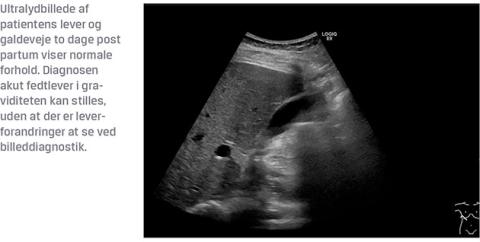

Efter tre dages behandling blev hun overflyttet til en hepatologisk afdeling, da hun opfyldte AFLP-Swansea-kriterierne (Tabel 1). For et positivt resultat af Swansea-kriterierne skal seks eller flere af de opstillede kriterier opfyldes (Tabel 1). Patienten opfyldte syv af kriterierne. Blodprøverne viste normaliseret ALAT-niveau, men stigende bilirubinniveau og let stigende laktatdehydrogenaseniveau. Der var fortsat påvirket nyrefunktion, men trombocytniveauet steg langsomt. Under indlæggelsen blev forløbet yderligere kompliceret af mekanisk ileus pga. dudenal fækulitis og infektion uden kendt fokus. En CT viste en ansamling foran uterus og serom i subcutis. Dette udviklede sig til en absces, der blev drænbehandlet. Seksogtyve dage post partum blev hun udskrevet med normale infektionstal og bedring af levertallene.

Ved kontrol fem en halv uge post partum var der normaliseret niveau af bilirubin og trombocytter, mens ALAT-niveauet fortsat var grænseforhøjet. Tre måneder senere var der normaliserede niveauer, og en fibroskanning med ultralyd viste ikke tegn til fibrosedannelse i leveren. Behandlingen afsluttedes således seks måneder post partum.